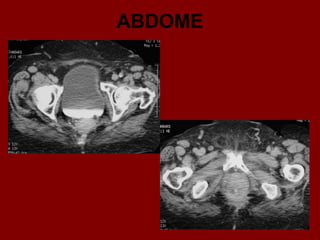

ABDOME